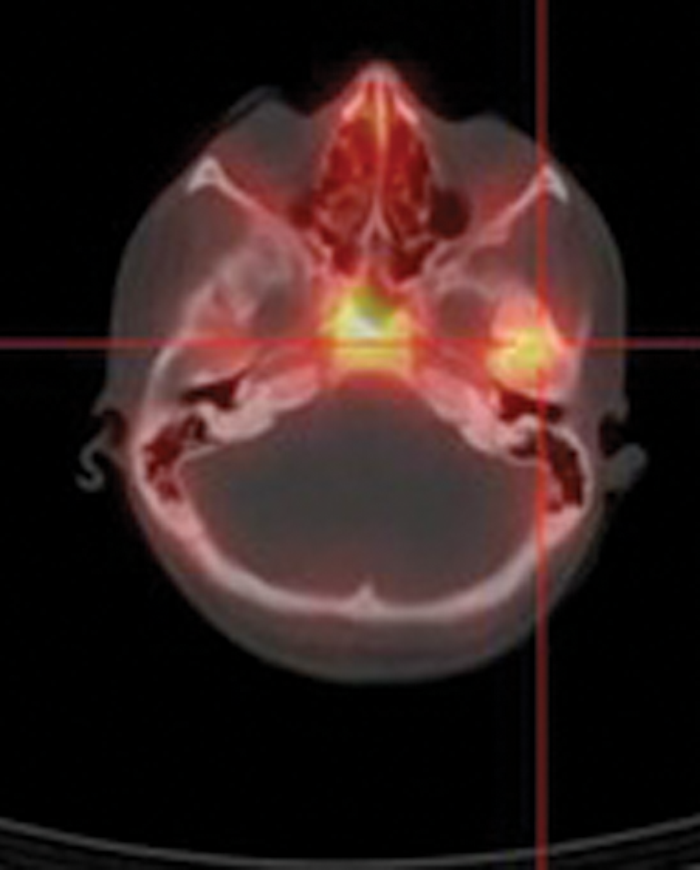

To date, no imaging modality provides a ‘gold standard’ for diagnosis and follow-up of SBO. CT allows good assessment of bone erosion and extracranial spread, both features of advanced disease; MRI offers good soft tissue evaluation including meningeal involvement and spread into medullary bone spaces [4]. However, neither of these modalities is particularly helpful in monitoring or follow-up due to persistence of anatomical alterations despite resolution of disease. Nuclear medicine techniques such as bone scintigraphy, indium-labelled white blood cell scans and gallium scans have traditionally been the mainstay of diagnosis and follow-up of patients with SBO. Scintigraphic bone scanning with technetium-99m methylene diphosphonate (99mTc-MDP) has high sensitivity for demonstrating increased osteoblastic activity and allows earlier diagnosis of osteomyelitis than CT imaging [5]. Bone scintigraphy remains positive for months even if there is no active infection and is therefore not useful in long-term monitoring of the condition. Indium and gallium-labelled radiopharmaceuticals accumulate in areas of active infection and can therefore be used for follow-up and prediction of resolution (Figure 1).

Figure 1: Axial CT and fused Indium-111 labelled white cell SPECT / CT images demonstrate abnormal accumulation of radio-labelled white cells localised to the right petrous temporal bone in a diabetic patient with SBO. Follow-up scan in six weeks post commencement of treatment showed persistent abnormal activity and a decision was made not to discontinue antibiotics. A repeat scan three months later showing no abnormality confirmed resolution.